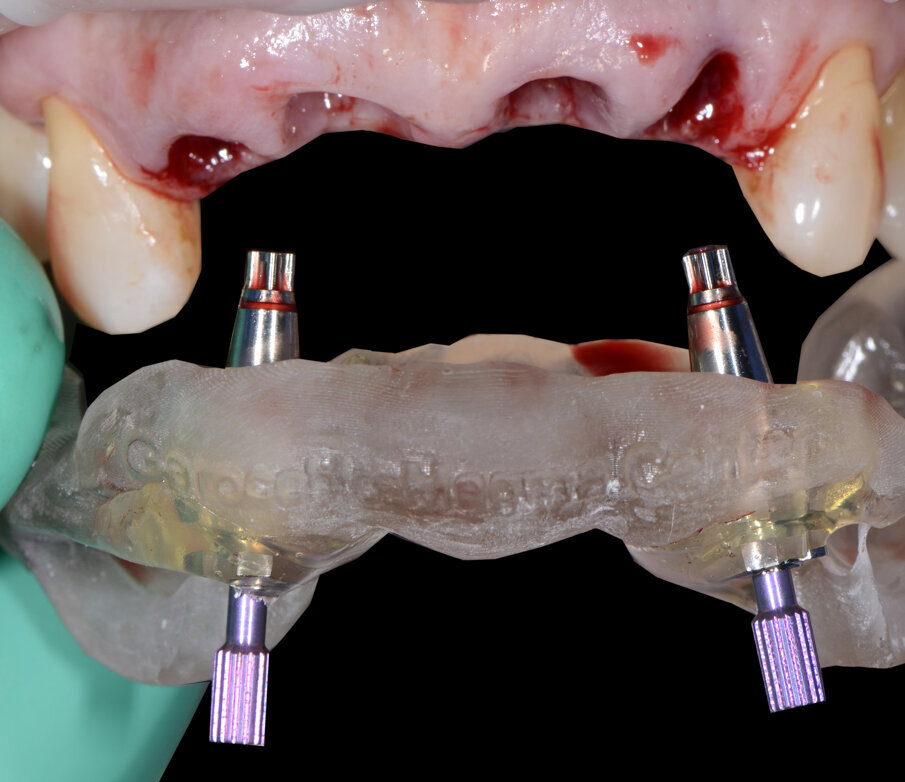

Alloggiamo la dima protesica (Fig. 33), e blocchiamo i transfert con della resina trasparente (tecnica DIL) (Figg. 34, 35). In questo modo possiamo far riposare il paziente in studio dopo appena 35 minuti dall’inizio dell’intervento. La dima protesica, infatti (Fig. 36) con i transfert inseriti viene completata con l’unione degli analoghi ai transfert (Fig. 37). L’insieme così composto viene riadattato sul modello master digitale iniziale (Figg. 38-40) sul quale era stata costruita sia la dima chirurgica che la dima protesica come anche il provvisorio. Gli analoghi vengono bloccati sul modello con resina trasparente (Figg. 41-43). Alloggiamo il provvisorio sul modello master digitale così ottenuto (Figg. 44, 45).

Fig. 35 - Rimozione dima protesica.

Fig. 36 - Dima protesica e transfert bloccati.

Fig. 37 - Dima protesica e transfert bloccati.

Fig. 38 - Riposizionamento sul modello master.

Fig. 39 - Alloggiamento definitivo